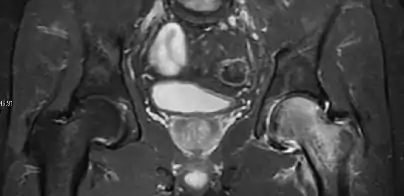

Radiological signs of transient osteoporosis of the hip include localized osteoporosis of the femoral head and neck (Figure 8). Nevertheless, final diagnosis has to be made with MRI to differentiate it from avascular necrosis and from insufficiency or stress fractures of the femoral head or neck. In case of AVN, radiographs can only demonstrate delayed or advanced signs. Staging according to Ficat classification ranges between normal appearance (stage I), slight increased density in the femoral head (stage II), subchondral collapse of the femoral head with or without “crescent” sign (stage III), and advanced collapse with secondary osteoarthritis (stage IV). In the case of stress or insufficiency fractures X-ray sensitivity has been proven to be much lower than MRI, which is currently the gold standard.[1]

Figure 8:

X-ray of a patient with transient osteoporosis of the left hip showing osteoporosis.[1]

Coronal stir imaging in transient osteoporosis, showing diffuse edema.[1]

Scintigraphy (A), sagittal T1 (B), and coronal PD fat sat of a patient with a subchondral fracture of the femoral head with convex shape to the articular surface.[1]

Coronal T1 of a patient with avascular necrosis of the femoral head.[1]

Intra-articular osseous causes of pain include several conditions: avascular necrosis (AVN), transient osteoporosis of the hip (TOH), tumors, and stress or insufficiency fractures. All these entities may present with a pattern of bone marrow edema characterized by decreased signal intensity on T1 weighted images and increased signal intensity on fluid sensitive sequences, such as fat saturated T2-weighted or STIR images. When there is no evidence of a focal lesion associated with the edema pattern, TOH is suspected. When a band of low intensity is seen inside the edematous area, the shape and length of this band become important. It is generally convex to the articular surface in the case of subchondral stress or insufficiency fractures, whereas it is concave, circumscribing all of the necrotic segment, in cases of AVN. When doubts do persist, gadolinium-enhanced MRI tends to show that the proximal portion beyond the band is enhanced in fractures but is not in AVN.[1]